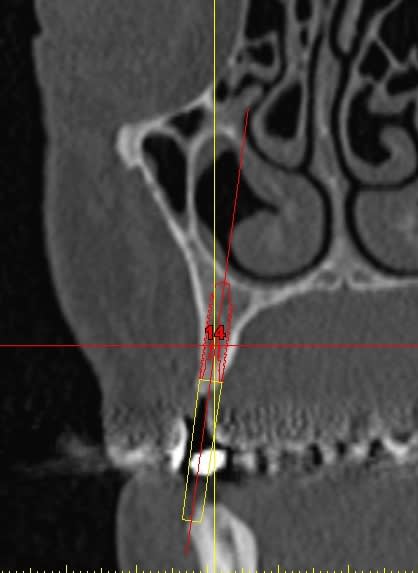

Pour l implant sur 14 il manque de l os en vestibulaire? Mise en place d os synthetique et membrane ou prelevement ramique?

Pour la 16 , une augmentation par abord lateral ou orthograde( desole je me souviens plus du nom de la technique).

> Pour l implant sur 14 il manque de l os en vestibulaire? Mise en place d os

> synthetique et membrane ou prelevement ramique?

Bonjour, pour la 16 ,tu peux faire une ostéotomie de SUmmers, tu as plus de 4 mm d'os .

Pour la 12 ou 13 utilise les expanseurs, prévoit un 3,6